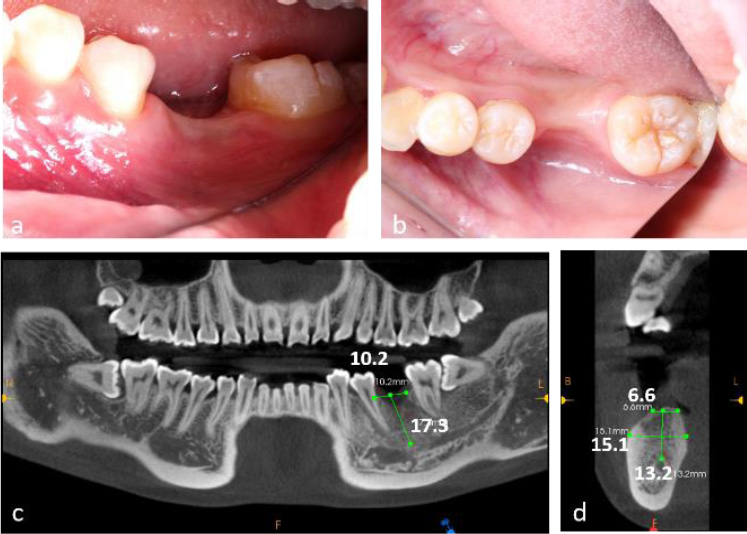

The patient demonstrated good oral hygiene, with a FMPS of 18% and an FMBS of 10%. The edentulous site showed buccal and vertical alveolar bone defects, with no adjacent tooth inclination or opposing tooth elongation (Fig. 1a, 1b).

Cone-Beam Computed Tomography (CBCT) revealed a 4 mm vertical bone defect and an alveolar crest width of 6.6 mm at the edentulous site. The distance from the alveolar crest to the mandibular canal was 13.2 mm (Fig. 1c, 1d). The third molar (tooth 38) was mesioangularly impacted.

Preoperative clinical and radiographic evaluation of a 23-year-old female patient presenting with tooth loss (#36) and concomitant alveolar bone atrophy. (a) Intraoral clinical photograph demonstrating buccal view of the edentulous area, (b) Intraoral clinical photograph showing occlusal view of the defect site, (c) Preoperative cone-beam computed tomography (CBCT) scans, (d) CBCT cross-sectional analysis revealing alveolar crest width of 6.6 mm and basal bone width of 15.1 mm at the edentulous site.